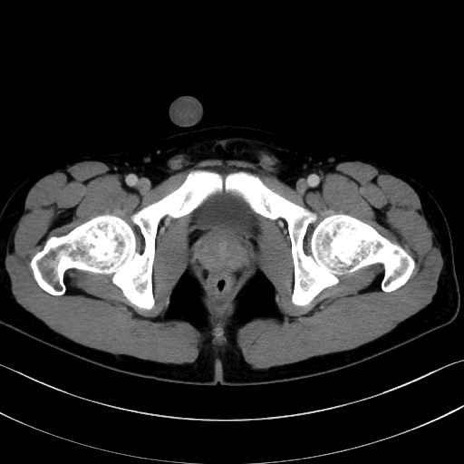

大殿筋 (Gluteus maximus)

中殿筋 (Gluteus medius)

小殿筋 (Gluteus minimus)

大腿筋膜張筋 (Tensor fasciae latae)

梨状筋 (Piriformis)